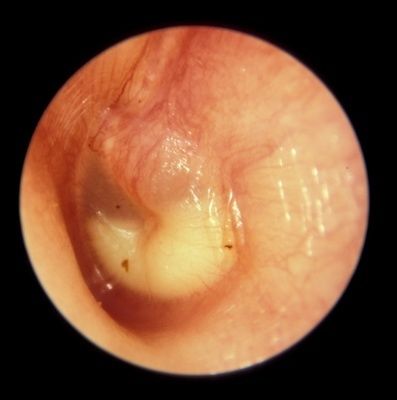

1. OTOSCOPIA NEUMÁTICA: Presencia de líquido en el oído medio

1. Signo precoz: Eritema Intenso pero por sí solo no sirve para el diagnóstico